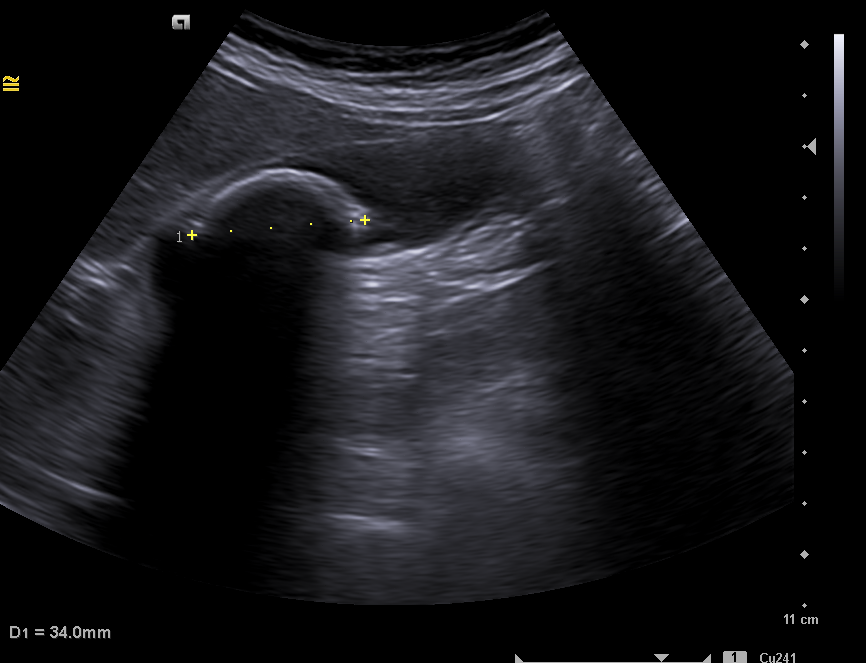

Ante la clínica se cita a la paciente en ayunas, para conseguir una máxima distensión de la vesícula.  Se observa una imagen hiperecogénica  móvil, con sombra acústica posterior compatible con litiasis de 35 mm. Sin colección perivesicular ni dilatación de la vía biliar intrahepática y extrahepática. Hígado con ecoestructura y ecogenicidad normal, sin LOES en su interior.  Hallazgos compatibles con litiasis vesicular gigante, descartando el diagnóstico de vesícula en porcelana.

Este caso nos permite entender la importancia de la realización de una ecografía clínica en adecuadas condiciones,  concretamente en la vesícula, debemos hacerlo de forma programada, para permitir su mejor replección y llegar a un correcto diagnóstico. El juicio clínico inicial parecía estar en concordancia con el de vesícula en porcelana por la falsa imagen de vesícula totalmente calcificada que, en realidad, producía esa litiasis gigante. Esto es importante para un adecuado manejo de las litiasis, ya que, en los pacientes asintomáticos, se recomienda colecistectomía en casos concretos con aumento de riesgo de cáncer de vesícula como presencia litiasis de gran tamaño (> 3 cm) o vesículas en porcelana.